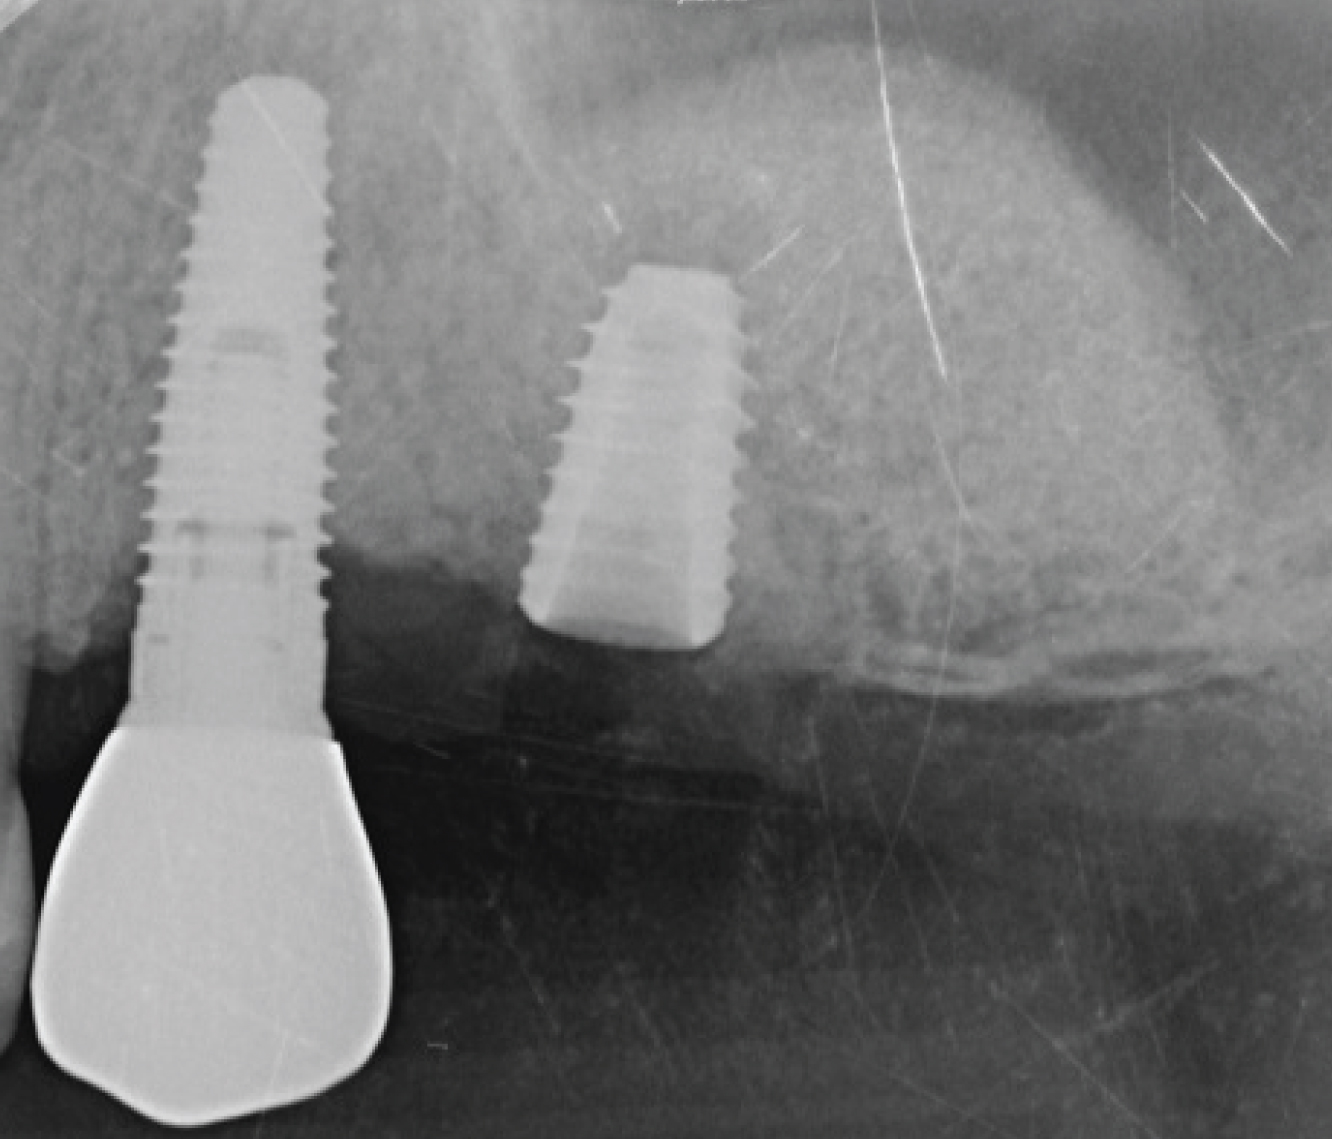

Director’s Clinical Cases

Director’s Clinical Cases